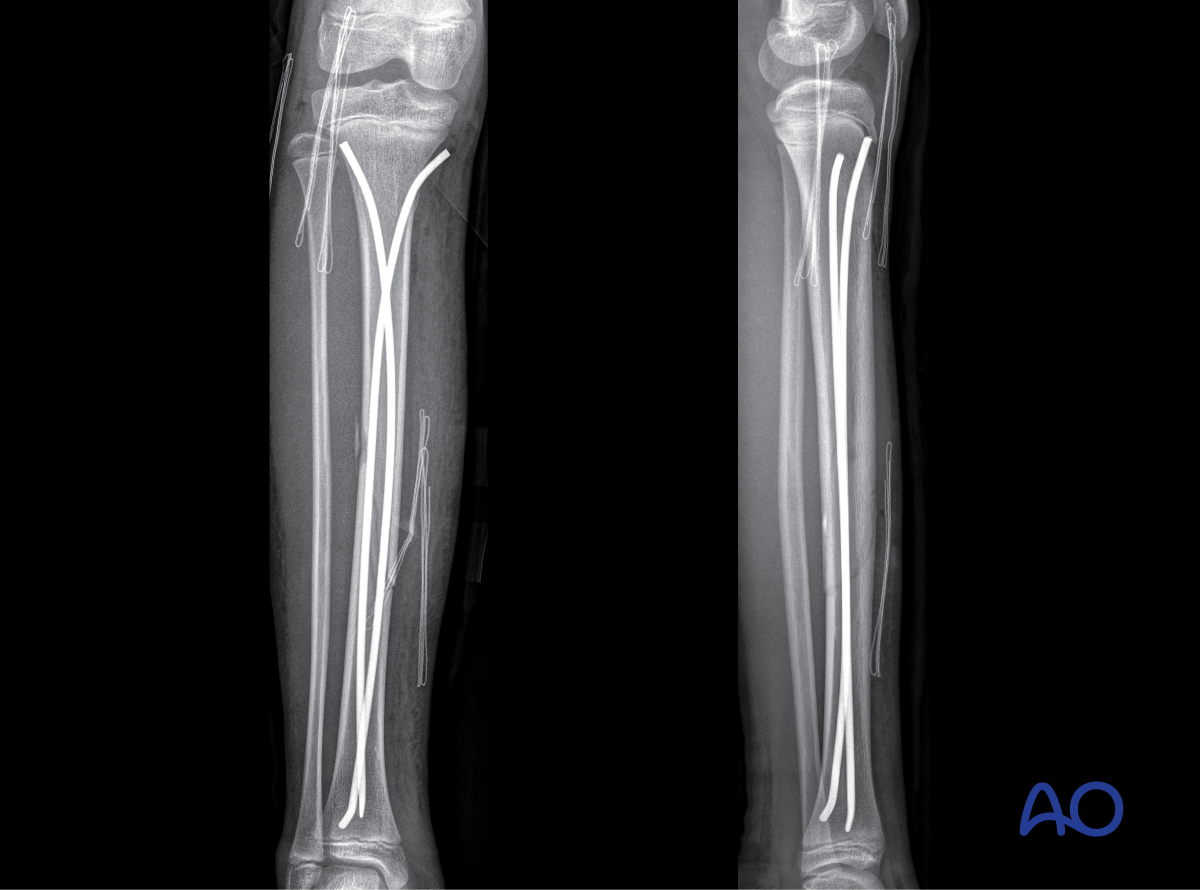

- Simple and multifragmentary fractures of the tibial shaft

This includes detailed procedures on elastic stable intramedullary nailing (ESIN), external fixation, and plate fixation, in addition to nonoperative management with casting and splinting.